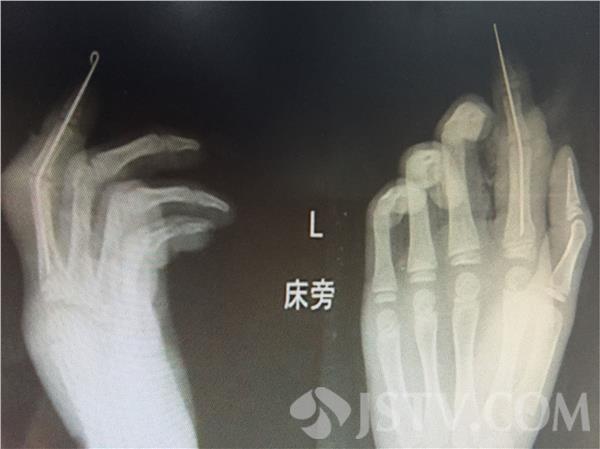

徐州仁慈医院外科主治医师介绍,小孩头咬得比较厉害,最主要是伤口非常乱,颅骨露外面了,另外两个手指,中指和食指咬断了。

经过抢救,目前孩子已无生命危险,但是由于孩子被狗咬伤,毁损污染严重,孩子的右手中指、食指前端已经无法再植,只能以后为其进行二次手术再延长。